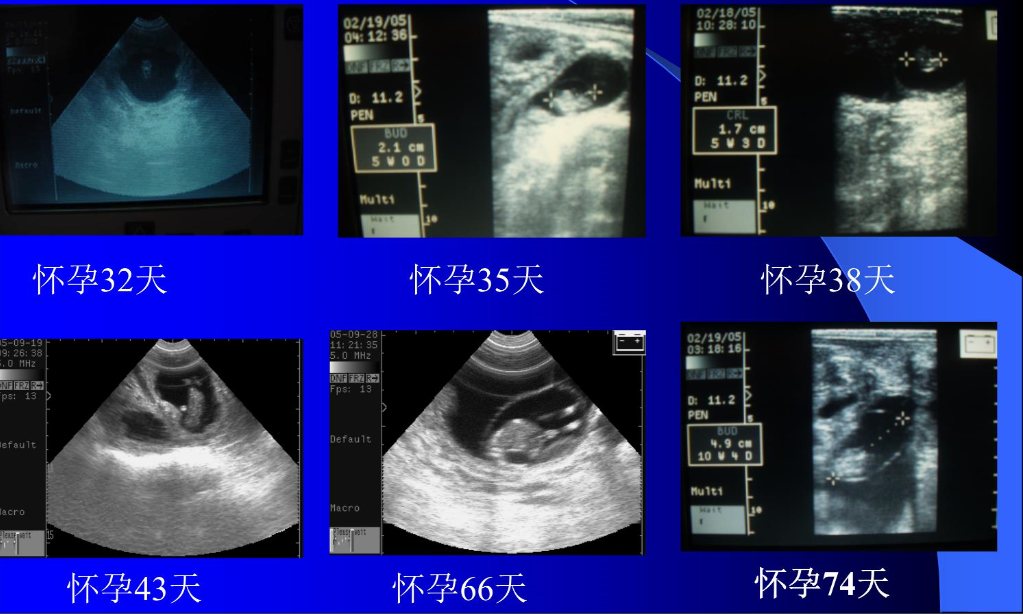

羊场的经济效益与羊的繁殖特点直接相关,兽用超声在母畜妊娠诊断方面发挥着十分重要的作用。通过超声检查,可以确定母羊的妊娠情况。现阶段,对于母羊妊娠的检查方法,比较常用是使用兽用B超机(羊用B超机)。 兽用B超机通常被用于动物的怀孕诊断、疾病诊断、···